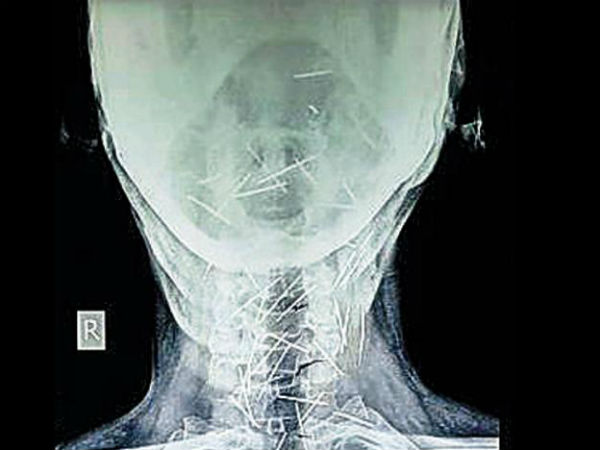

സര്ജറിയുടെ ആവശ്യത്തിനായി എക്സ്റെ എടുത്തിയിരുന്നു. എന്നാല് എക്സറെയില് തെളിഞ്ഞത് ശരീരത്തിനുള്ളിലുണ്ടായ 76 മൊട്ടു സൂചികളായിരുന്നു.ശരീരത്തിന്റെ വിവിധഭാഗങ്ങളാലായിട്ടാണ് മെട്ടുസൂചികള് കണ്ടെത്തിയത്. ശരീരത്തിന്റെ തൊലികള്ക്കുള്ളിലായാണ് സൂചികള് എല്ലാം എക്സറെയില് തെളിഞ്ഞത്. കഴുത്തിലും കൈയിലും കാലിലുമണ് പിന്നുകളിലധികവും കണ്ടെത്തിയത്.

റെയില്വെ ജീവനക്കാരനായ മീണയുടെ ശരീരത്തില് എങ്ങനെയാണ് മൊട്ടുസൂചികള് എത്തിയതെന്ന് അറിയില്ല. മാറ്റാരെങ്കിലും ബോധംകെടുത്തിയ ശേഷം മീണയുടെ തൊലിപുറത്തു കയറ്റിയതാണെങ്കില് മുറുവിന്റെ പാടുകള് ശരീരത്ത് കാണുമായിരുന്നു. എന്നാല് ഇയാളുടെ ശരീരത്ത് മുറിവിന്റെ പാടുകളൊന്നുതന്നെയില്ലാ. എന്നാല് ഇത്രയുമധികം മൊട്ടു സൂചികള് ശരീരത്തിലുണ്ടായിട്ടും അന്താരവയവങ്ങളിലൊന്നും തന്നെ ഇവ എത്തിയിട്ടില്ലയെന്നതു ഡോക്ടര്മാരെ കുഴക്കുന്ന ചോദ്യമാണ്.

മീണ സൂചികള് വിഴുങ്ങിയിരുന്നെങ്കില് അവ എത്തേണ്ടിയിരുന്നത് വയറിനുള്ളിലോ അന്നനാളത്തിലേയായിരുന്നുവെന്നു മീണയെ ചികിത്സിച്ച കോട്ട റെയില്വെ സ്റ്റേഷനിലെ സര്ജന് പറയുന്നു.കൂടാതെ പ്രമേഹ രോഗിയായതില് സര്ജറി നടത്തി മൊട്ടു സൂചികള് പുറത്തെടുത്താല് മീണയുടെ ജീവനെ തന്നെ ബധിക്കുമോ എന്നതില് ഡോക്ടര്മാര്ക്ക് ആശങ്കയുണ്ട്.

സര്ജറി ചെയ്ത് സൂചികള് പുറത്തെടുത്തല് അത് മീണയുടെ ജീവനെ ബാധിക്കുമെന്ന് ഡോക്ടര്മാര്ക്ക് ആശങ്കയുണ്ട്.